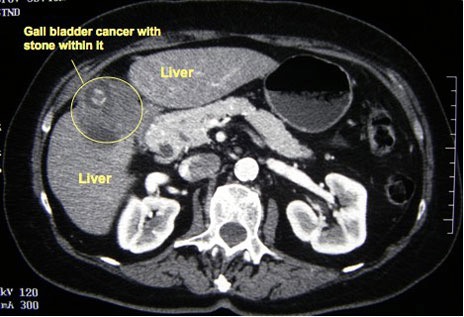

Spiral CT scan probably gives the best estimate of the extent of disease. However, MRI scanning gives equally high-resolution images, with the additional benefit of providing an MRCP. CT and MR usually give adequate information about the localblood vessels, and hepatic angiography is rarely indicated.

CT scan picture showing a cancer that has arisen from the gall bladder. A gallstone can also be seen -